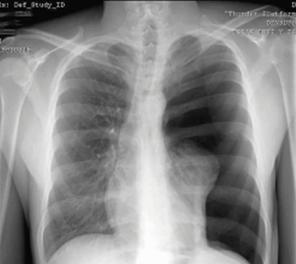

Derrame pericárdico severo da imagen en botellón en la radiografía de tórax. (ENAM EXTRA 2021)

Radiología:

Cardiomegalia

Radiografía: cardiomegalia con hipertensión venosa pulmonar